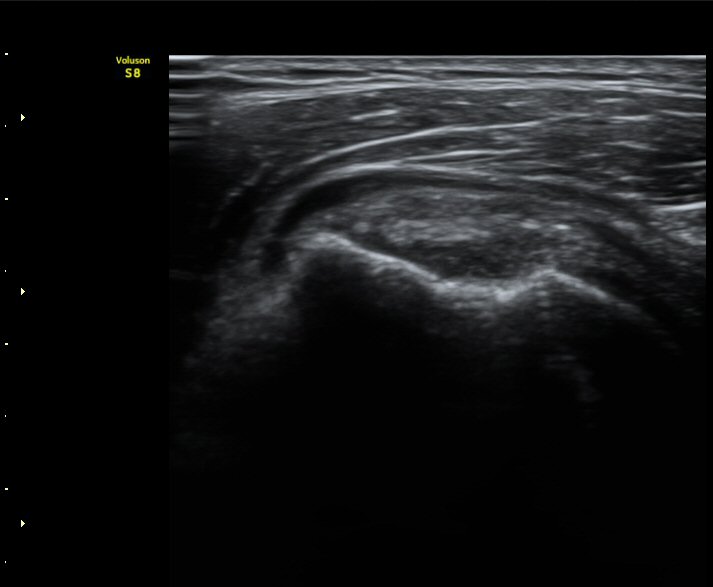

ÃÊÀ½ÆÄ °Ë»ç

2049205267_d18eca99_IMG_20140331_2_1-c.jpg